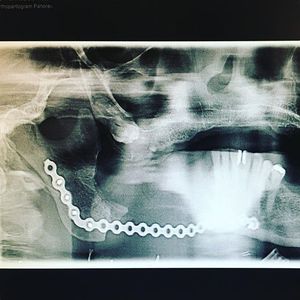

Partial resection of the mandible due to osteomyelitis Part II πŸ‘¨β€βš•οΈβš™οΈπŸ”¨Β

After the surgical resection, a titanium reconstruction plate is used to reconstruct the contour of the jaw. This type of infection generally requires 6 weeks of IV antibiotic treatment πŸ’‰πŸŒ‘